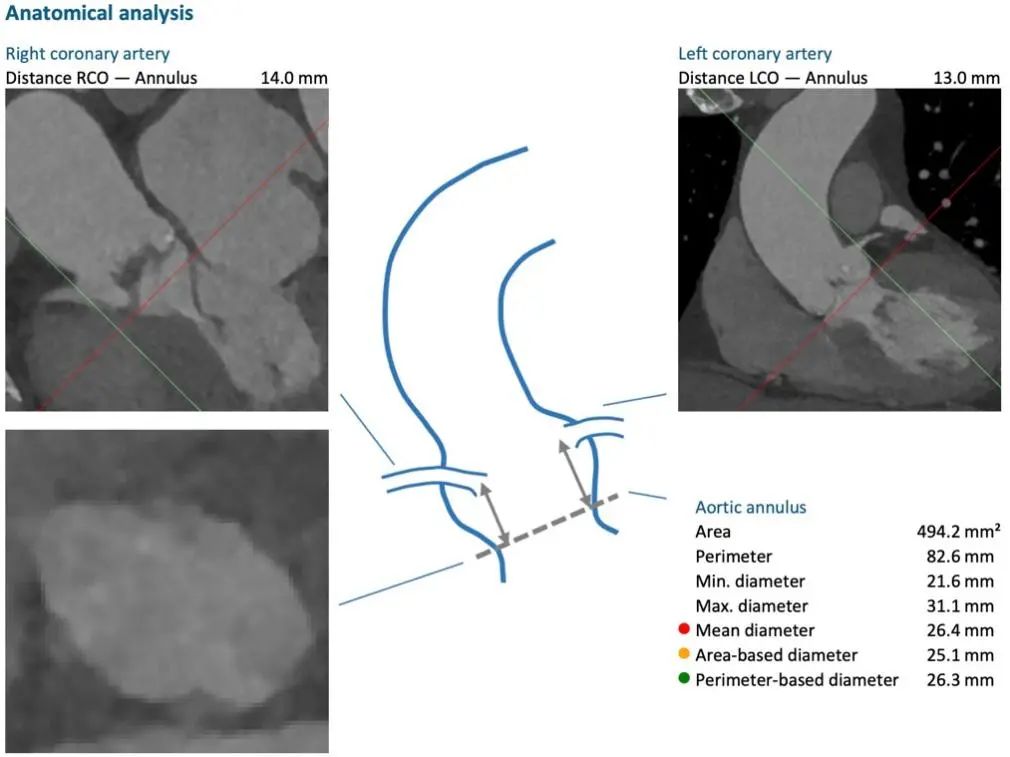

患者术前评估而团队常规开展的经皮导管主动脉瓣置入术(TAVR),无需开胸、无需心脏停跳、无需切开心脏,只需要大腿根部一个6mm的穿刺点,即可完成心脏大门的置入,解决病人的问题。